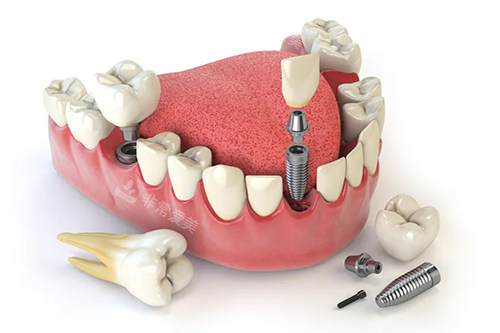

牙齿种植卡通示意图

牙齿种植牙模型卡通示意图